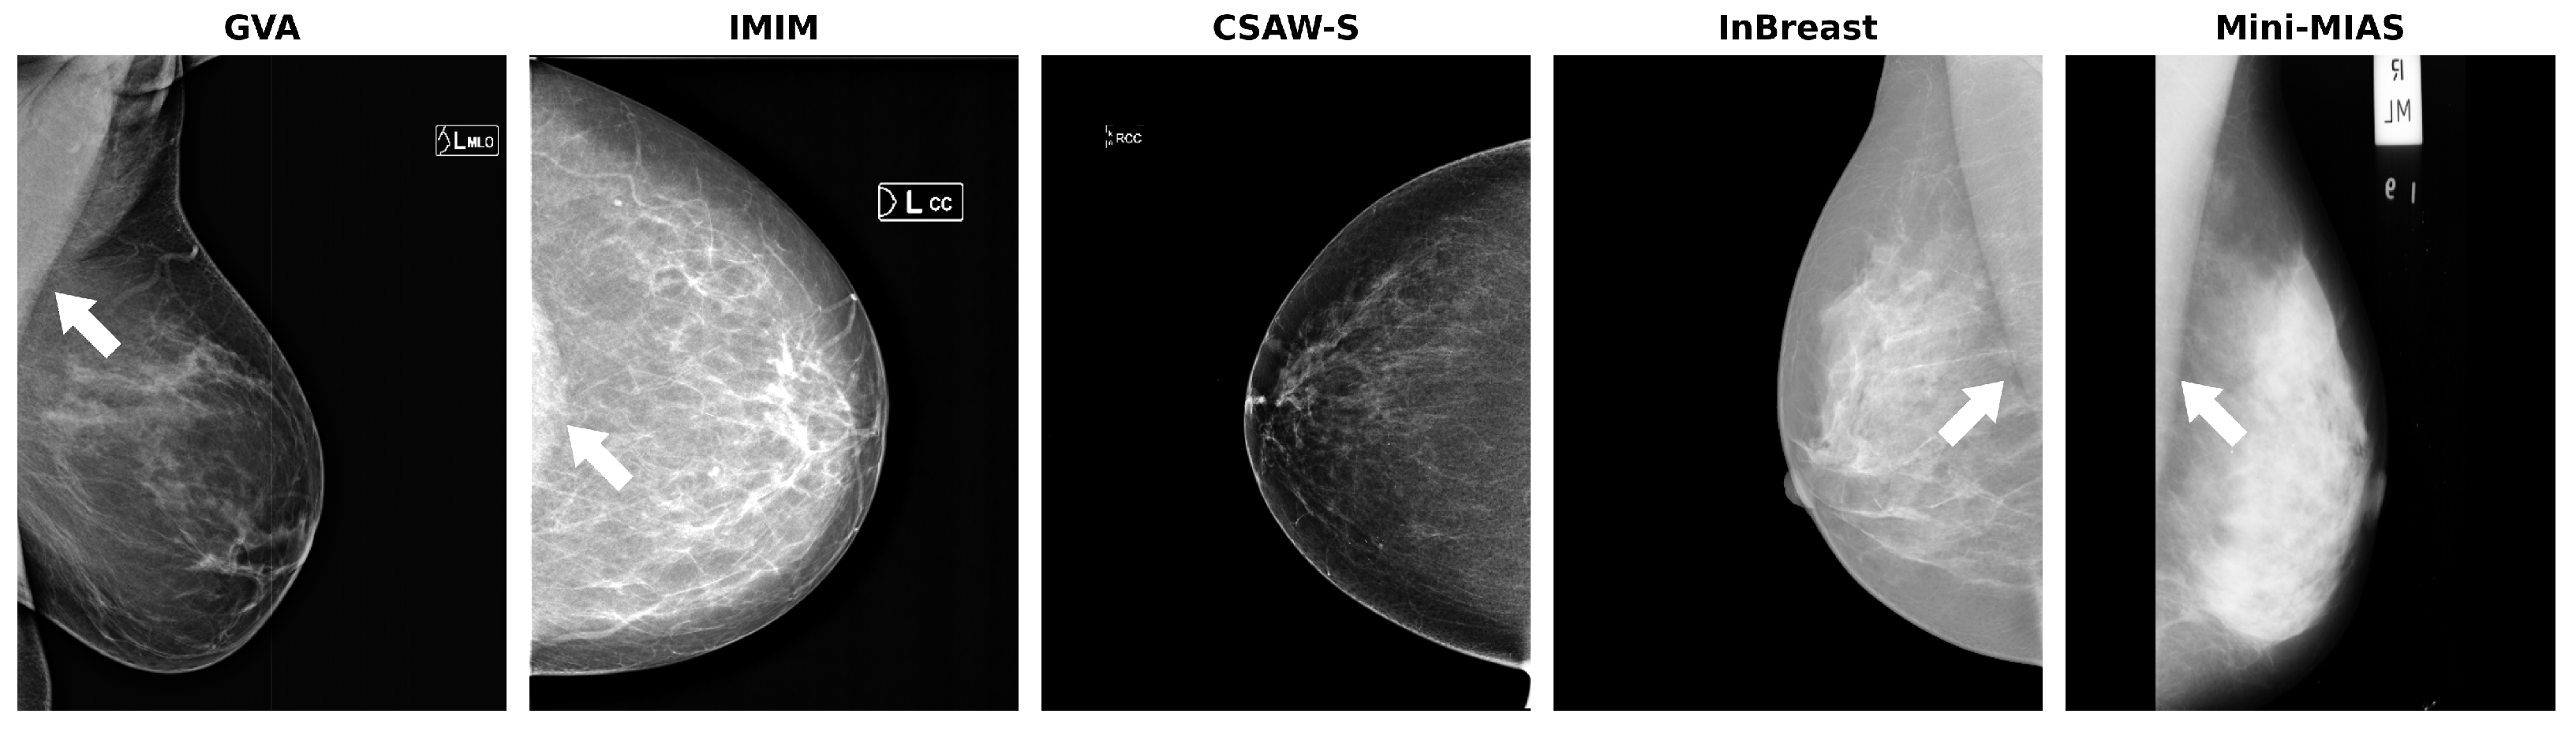

A summary of the datasets is presented in Table 1, showing the number of images per view available in each split. Examples for each dataset are shown in Figure 1.

Figure 1.

Sample images for each dataset. The white arrows indicate the pectoral muscle. Note the presence of the pectoral muscle in the cranio-caudal (CC) view of the IMIM dataset (second image).